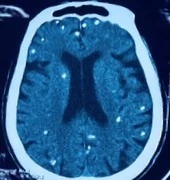

Ở người, ngoài vị trí cơ, nang sán có thể được hình thành tại các vị trí nguy hiểm như não, mắt, có thể gây ra động kinh, rối loạn tâm thần...